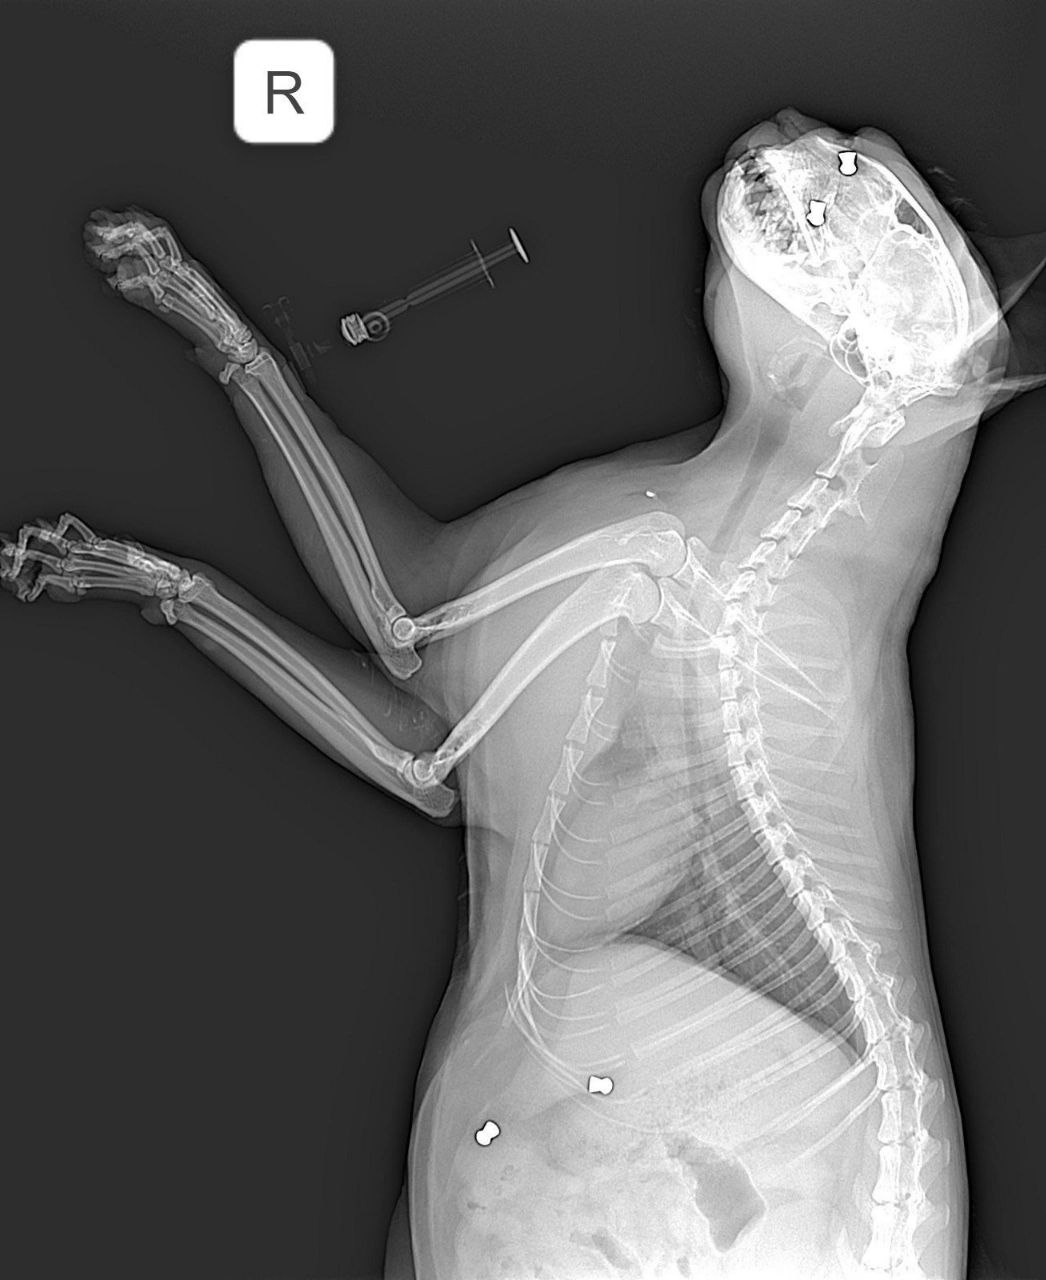

В Арзамасе неизвестный расстрелял кота из «воздушки». Кот ушёл гулять, а вернулся со множеством пуль по всему телу.

Ветеринар заключил, что пушистика привязали, чтобы он не убегал, и стреляли в него. Бедняга сейчас в больнице в тяжёлом состоянии.